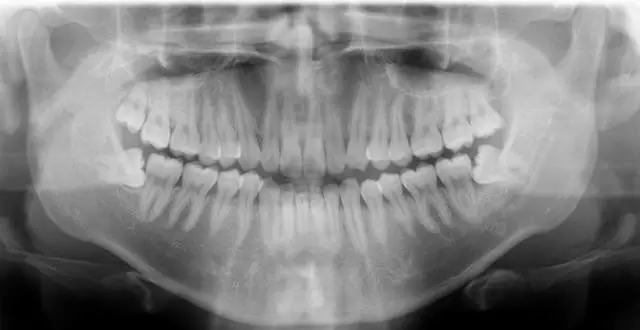

萌出時間關(guan) 鍵 照個(ge) 牙片做到心中有數

雖然萌出的時間不同,但17歲-19歲這個(ge) 年齡段去做一次口腔X光片卻至關(guan) 重要。“12歲時立事牙就存在於(yu) 牙胚中,17歲左右開始萌出,但不論萌出還是不萌出,都要做一次口腔X光片,這樣才能了解牙胚中立事牙存在的狀態和未來可能存在的問題。”深圳牙科醫院愛康健口腔醫院醫生建議。